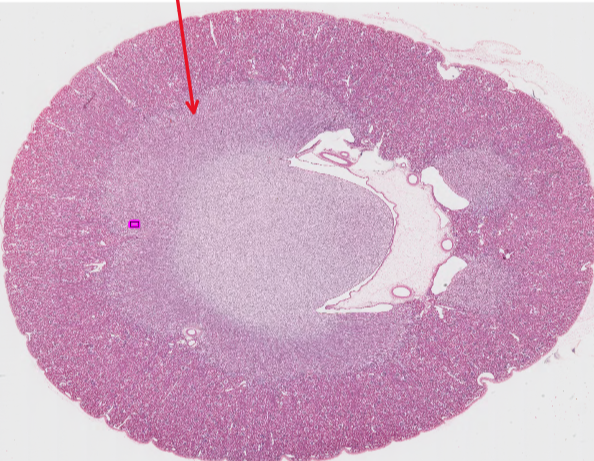

This is a kidney, identify this structure:

Cortex

precortex

medulla